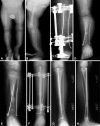

The results of treatment of congenital pseudarthrosis of the tibia (CPT) are frequently unsatisfactory because of the need for multiple operations for recalcitrant nonunion, residual deformities, and limb-length discrepancies (LLD). Although the etiology of CPT is basically unknown, recent reports suggest the periosteum is the primary site for the pathologic processes in CPT. We hypothesized complete excision of the diseased periosteum and the application of a combined approach including free periosteal grafting, bone grafting, and intramedullary (IM) nailing of both the tibia and fibula combined with Ilizarov fixation would improve union rates and reduce refracture rates. We retrospectively reviewed 20 patients at two centers. The minimum followup was 2 years (mean, 4.3 years; range, 2-10.7 years). Union was achieved after the primary operation in all patients. Ten refractures occurred in eight of the 20 patients (two each in two patients, one each in six patients). Seven patients underwent seven secondary surgical procedures to simultaneously treat refracture and angular deformities. We used bisphosphonate as adjuvant therapy in three patients with refracture without subsequent refracture. We performed no amputations in these 20 patients. All patients were braced through skeletal maturity. Combining periosteal and bone grafting, IM nailing, and Ilizarov fixation is an effective treatment. IM nailing decreases the severity of subsequent fracture.